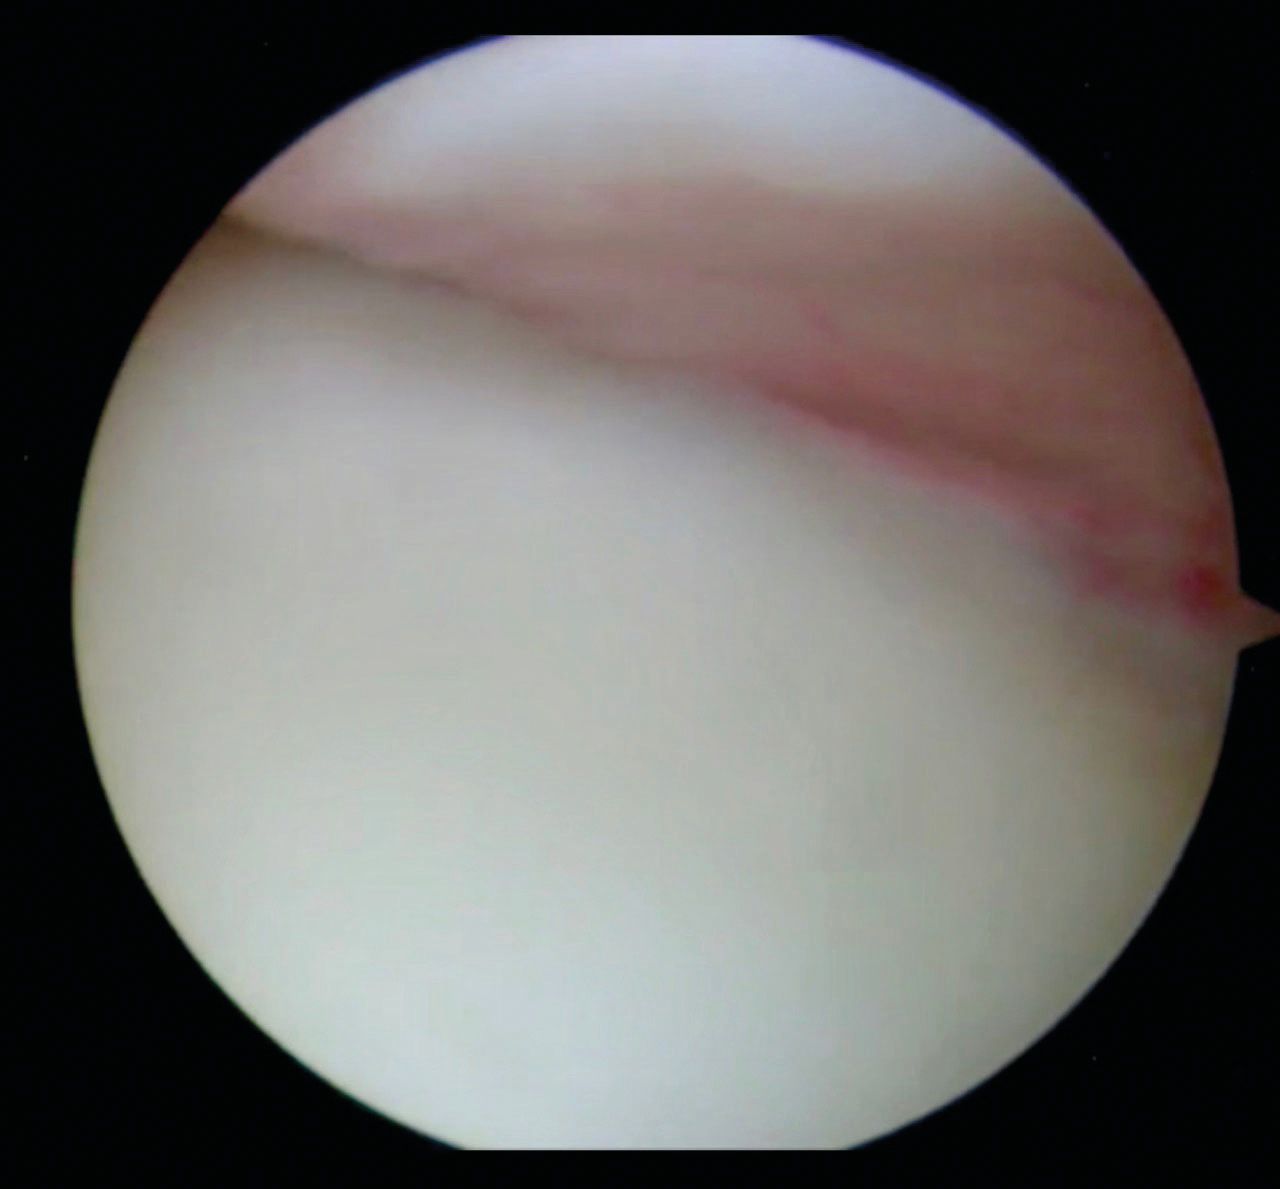

The posterior lateral humeral defect was first described by Malgaigne in 1855, then by Broca and Hartmann in 1890. It was then classified by Hill and Sachs in 1940 [10] and this is the usual name nowadays. The Hill-Sachs defect is a posterior lateral compression fracture on the humeral head which happens during an anterior dislocation when the glenoid anterior rim hits the posterior part of humeral head. Figure 1.

It is located at the posterior aspect of the humeral head. Usually, a small HSL is located close to the greater tuberosity attachment of the infra-spinatus, whereas a large HSL extends more medially.

The concept is to fill (remplissage means filling in french) the humeral defect with soft tissue (posterosuperior capsule along with the infraspinatus tendon). The healing process of the capsule in the defect will convert the intra-articular Hill-Sachs lesion in an extra-articular lesion incapable of engaging with the glenoid. This procedure is combined with the treatment of the anterior capsulo-labral lesion (Bankart). The two procedures are concomitant and performed arthroscopically. Figure 3.